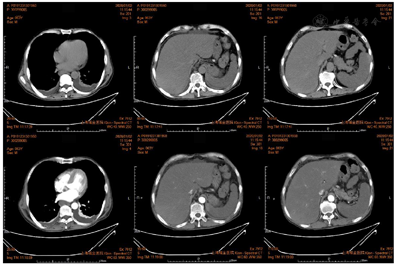

血常规、血生化、凝血功能指标详见表1。尿常规(2020-01-01):蛋白质(+),尿胆原(±),胆红素(+++),潜血(+),甲、乙、丙、丁、戊型肝炎病毒抗体均阴性,巨细胞病毒、EB病毒、单纯疱疹病毒抗体、呼吸道九联、梅毒抗体、抗HIV均阴性。自身免疫性肝病相关抗体均阴性。肿瘤标志物(2020-01-02):CA125 412.5 ↑ U/mL,CA199 145.1 ↑ U/mL,余均正常。甲状腺功能(2020-01-02):T3 0.55 ↓ nmol/L,T4 48.27 ↓ nmol/L,余均正常。上腹部+盆腔CT增强(2020-01-02)(图1):脾梗死;脂肪肝;胆囊壁水肿;两肾多发囊肿;腹腔积液,引流中;两侧胸腔积液并两肺下叶膨胀不全;食管下段、贲门周围多发血管影;右侧第11肋骨陈旧性骨折。胸部CT(薄层)增强(2020-01-02):双侧胸腔积液,两肺下叶膨胀不全;少量心包积液。门静脉薄层CTA增强(2020-01-02):门静脉未见明显异常。食道胃底静脉曲张。脾梗死;脂肪肝;胆囊壁水肿;两肾多发囊肿;食管下段右侧缘、腹腔少量积液,引流中。